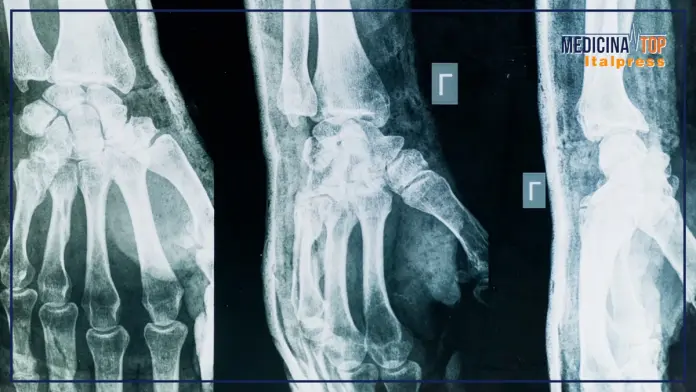

La riflessione di Selmi si sofferma su due aspetti: riconoscimento della malattia e fattori di rischio. “La diagnosi di artrosi si fa tuttora con la semplice radiografia; il consumo di cartilagine di uno dei due capi ossei porta un avvicinamento delle due ossa all’interno dell’articolazione e si ha l’artrite reumatoide, che può essere intercettata prima e trattata con efficacia. La prima localizzazione tipica dell’artrosi è la schiena: se facciamo una radiografia della colonna lombare o cervicale a chiunque abbia più di cinquant’anni troveremo segni di artrosi in tutti, ma per fortuna non tutti ne soffrono; dopo la localizzazione della colonna si passa alle mani. I fattori di rischio più importanti sono per l’artrosi familiarità, genere femminile, età avanzata e sovrappeso, indipendentemente dalla localizzazione; per l’artrite reumatoide familiarità, genere femminile e fumo di sigaretta; per l’artrite psoriasica la presenza di psoriasi”.

– foto tratta da video Medicina Top –